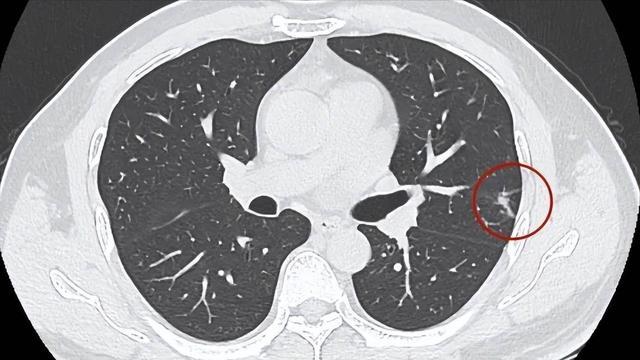

先明确一个中枢事实,9mm肺结节属于中等大小结节,既不属于无需贯注的轻细结节,也并非确诊恶性的高危结节,这个阶段是逆转的黄金期,一朝错过,结节延续增大就会增多打扰难度。

分离结节性质是第一步,必须依靠专科的肺部影像学检查,齐集肿瘤象征物筛查,由专科医师判断良恶性,切勿自行把柄结节大小判断,更弗成轻信偏方、秘方盲目调养。